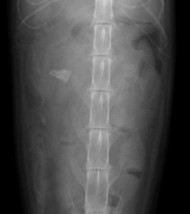

超音波検査およびレントゲン検査

腎結石の増大および腎盂の拡張を認めた

右腎臓内に巨大な結石の陰影が認められる